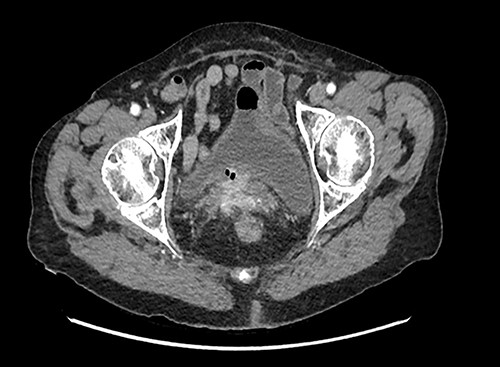

A 90-year-old woman presented with abdominal pain and pneumaturia; in her medical history we find a laparotomy mesh rectopexy 15 years ago. CT scan showed inflammation around the mesh that can also be seen entering the bladder (Figs 5 and 6).

While cystoscopy showed the presence of the mesh in the urinary bladder, rectoscopy visualized the mesh on the anterior wall of the rectum at 3 cm from the anal marge.

CT scan of abdomen and pelvis with contrast helps in localizing the mesh as well as the presence of any pelvic collection, severity of inflammation around the area of mesh and erosion into adjacent viscera [2].